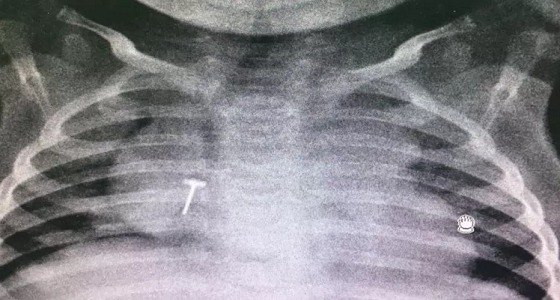

إنقاذ رضيع ابتلع جسم معدني بـ ” سعود الطبية “

منذ 7 سنة

0

3503